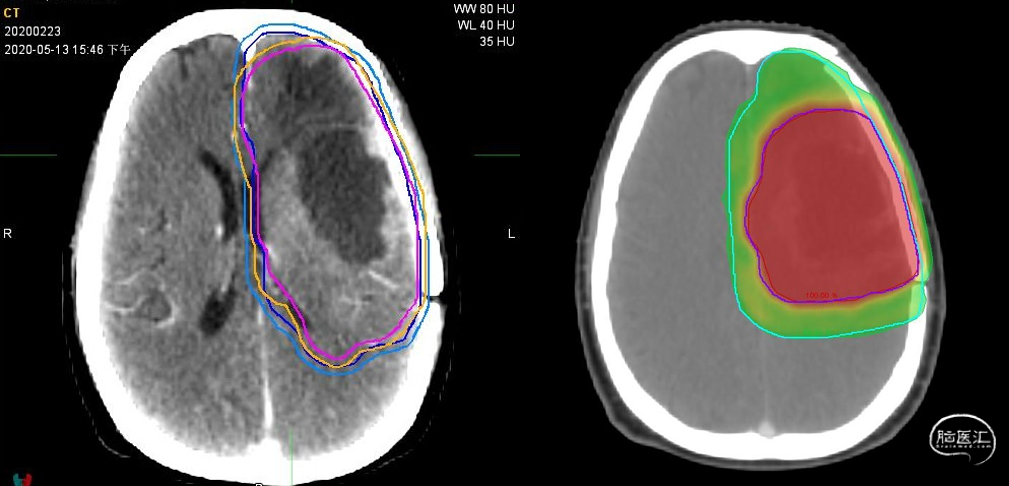

放疗靶区勾画:图示。

针对次预后差的患者实施术后标准的TMZ同步放化疗及早期电场治疗(TTFields)(同步放化疗后10余天开始)+辅助TMZ,治疗合理、规范。TTFields治疗肿瘤的原理是特定频率的交变电场,通过干扰肿瘤细胞有丝分裂过程中细胞内带电粒子和极化分子的运动,导致肿瘤细胞内部的一些结构无法正常形成,甚至造成细胞膜破裂,诱导有丝分裂期的肿瘤细胞凋亡。临床研究已经显示在新诊断、复发胶质母细胞瘤明确疗效,TTFields联合TMZ可以显著延长新诊断的GBM患者的PFS和OS,被各大胶质瘤指南明确推荐。研究数据显示,肿瘤电场治疗疗效与依从性密切正相关,当患者每天穿戴超过22小时,五年生存率可提升至29.3%,较单用TMZ辅助治疗明显提高。